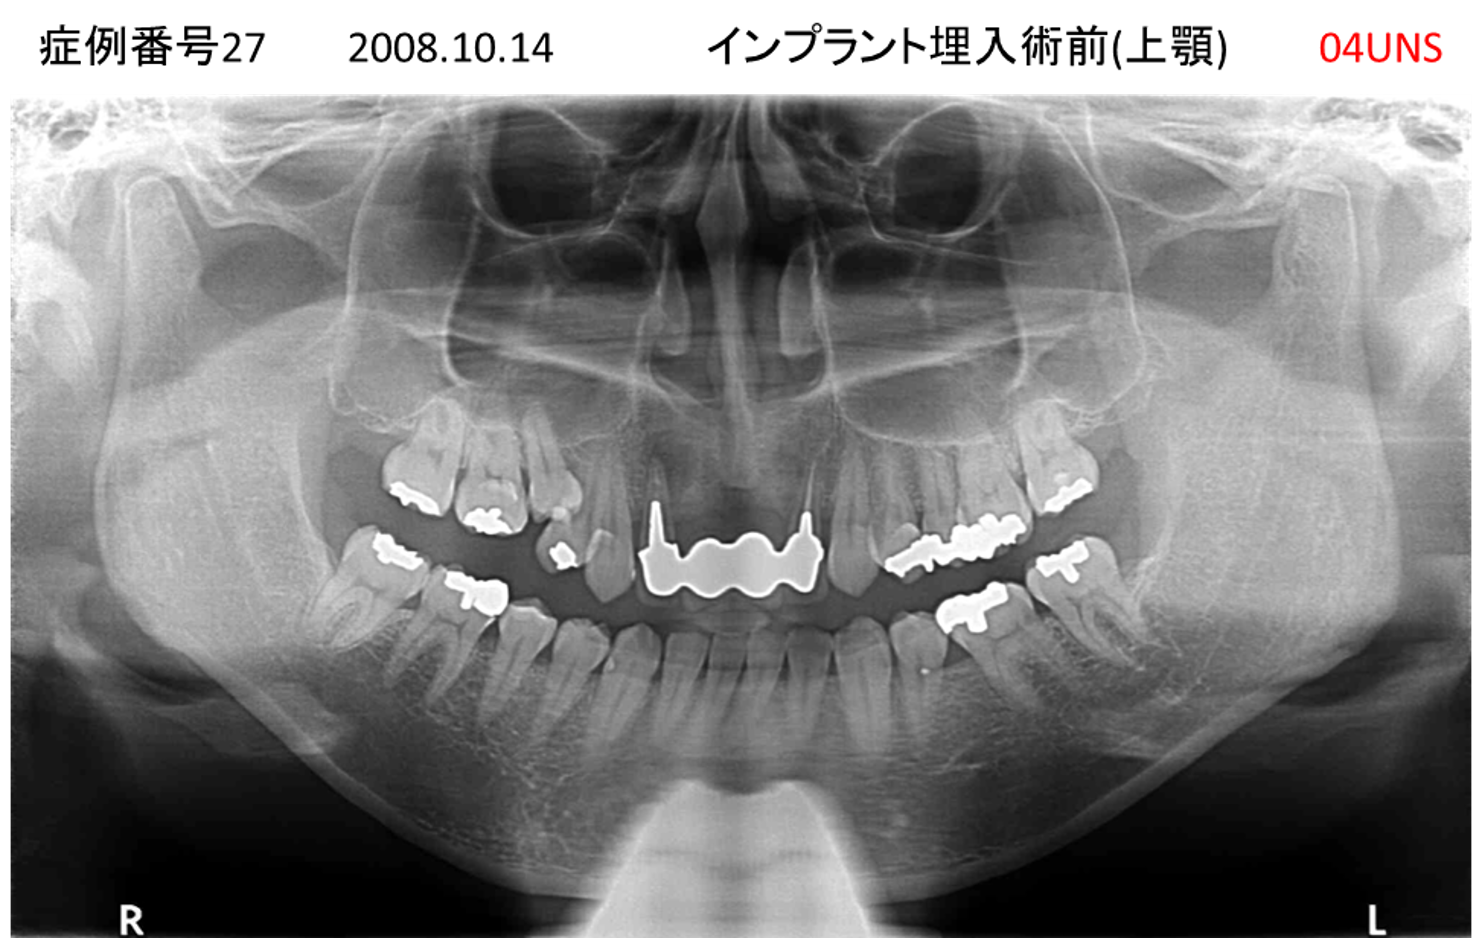

奥歯で噛めない患者様のインプラント症例

| 治療名称 |

インプラント |

| 治療費用 |

200万円+税 |

| 治療期間 |

4か月 |

| 患者さんの症状(主訴) |

奥歯で噛めない。 |

| 治療内容 |

| 治療結果 |

固いものもしっかり噛める。見た目がとても良くなった。 |

| 治療の注意点(リスク/副作用) |

インプラントが壊れたら再治療が必要 |